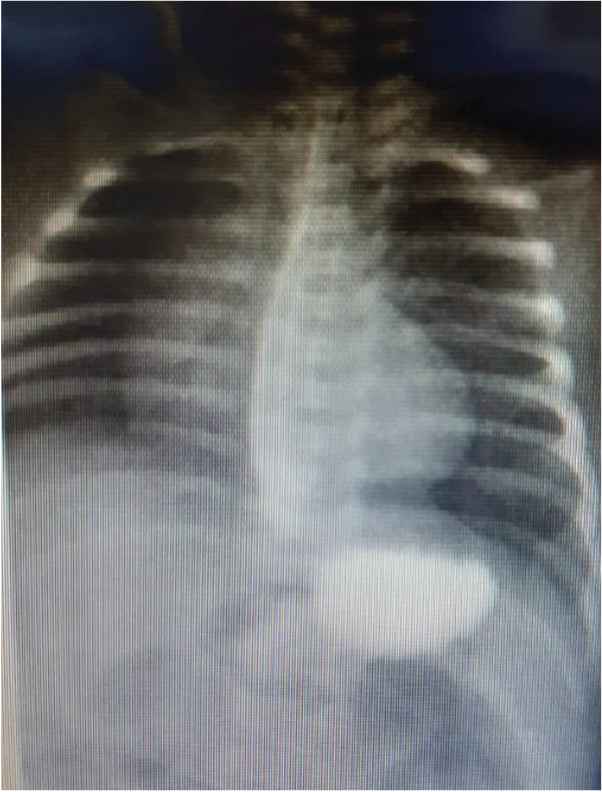

A full-term male with an unremarkable antenatal and perinatal history admitted on the date of birth to the Neonatal Intensive Care Unit (NICU) because of transient tachypnea of the newborn. During his stay, he developed episodes of hypoglycemia and intermittent yellow to green vomiting. There were no significant findings in the abdominal Ultrasound (US) and X-ray. He was discharged against medical advice as requested by the mother on the 3rd day of life. The baby stayed at home for 4 days with a history of intermittent vomiting. He was later readmitted to the NICU because of recurrent bilious vomiting and clinical jaundice on the 7th day of life. During his stay, he developed episodes of hypoglycemia and received phototherapy for prolonged jaundice and was kept Nill per oral (NPO) initially. Trials to resume feeding were always associated with intermittent vomiting, which was sometimes bilious or fecal. The result of abdominal examination was unremarkable. Interestingly, there was no distension, and the baby passed stool frequently. All workup to rule out sepsis, including metabolic disorders, were benign. Moreover, imaging studies, including abdominal US, X-ray, and upper and lower gastrointestinal tract contrast study (Figures 1–6, respectively), all revealed nonsignificant findings. Eventually, an explorative laparotomy was performed on the 17th day of life, which showed ileal stenosis (Figure 7), 32 cm from the ileocecal valve. The stenotic area was resected, and end-to-end anastomosis was carried out. Feeding was slowly started on the 5th postoperative day. He gradually reached full feeding with no vomiting and was discharged home on the 27th day of life and has been well since then.

Barium meal – 30 min.

In congenital intestinal atresia, radiographic examination of the abdomen with X-ray and contrast studies is a useful diagnostic tool. For proximal jejunal and ileal atresia, the presence of a few dilated proximal bowel loops with no distal gas is observed. Intraperitoneal calcification can be seen in prenatal bowel perforation or meconium peritonitis [6]. Malrotation is ruled out using an upper gastrointestinal series contrast study. A contrast enema is used to reveal the atypical appearance of the colon, as may be seen in meconium ileus or Hirschsprung disease. If the contrast passes into the dilated loop of bowel, then atresia is ruled out. Ileal stenosis can be distal or proximal; in the case of proximal ileal involvement, the colon is usually normal in size as sufficient succus entericus reaches the colon from the small bowel distal to the obstruction as in our case; however, in distal involvement, it is generally unused and microcolon less than 1 cm in diameter is seen. Thus, clinicians should always consider the possibility of congenital intestinal stenosis in any newborn with unexplained vomiting even if the radiological data are not significant. The prognosis is excellent if treated with surgery.